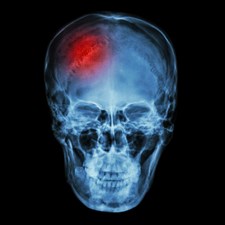

Hundreds of thousands set to benefit as NICE final draft guidance recommends new treatment to prevent heart attacks and strokes in people with raised blood fats

NICE has today (10 June 2022) published final draft guidance which recommends icosapent ethyl for reducing the risk of cardiovascular events such as heart attacks and strokes in adults who have raised levels of a type of blood fat called triglycerides.